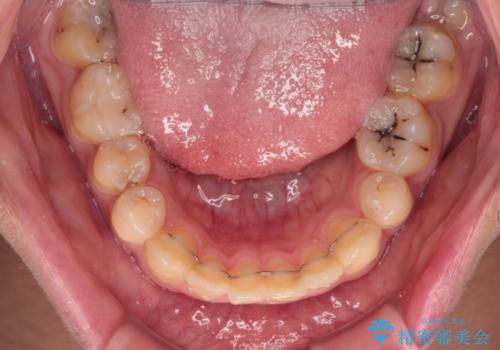

矯正治療後は上顎前歯4本をオールセラミッククラウンにて補綴治療を行うこととしました。

むし歯が多かったため、ワイヤー矯正中に処置したむし歯が悪化することが懸念されましたが、歯磨きをしっかりと行ってくれたため、とても良好な状態を維持することができました。